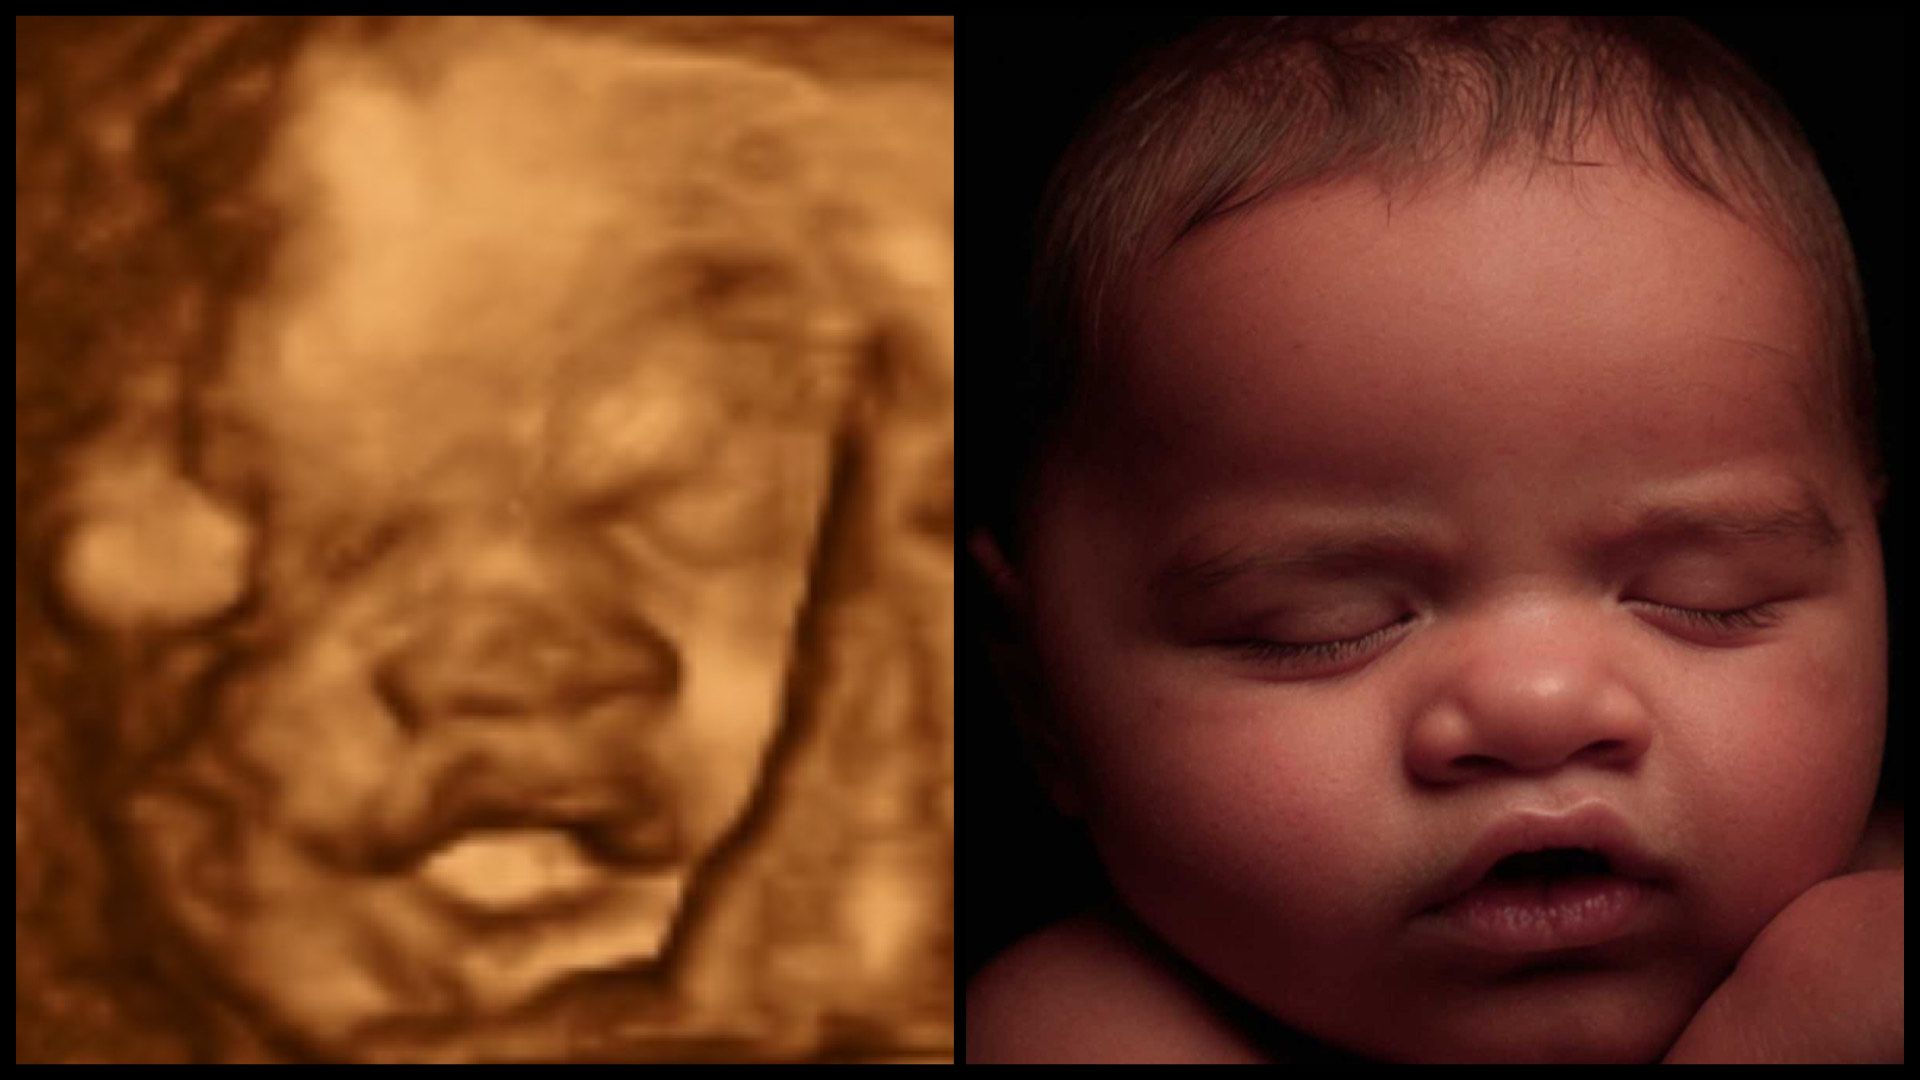

Most Realistic & lifelike photo you can get until the arrival of your little one. Using the newest technology to change your 3d/4d photo into something more realistic without changing any of your baby's features.